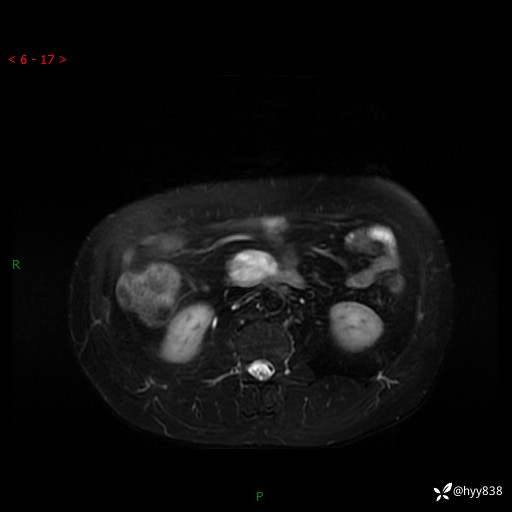

MRI(T1WI+T2WIfs+DWI)